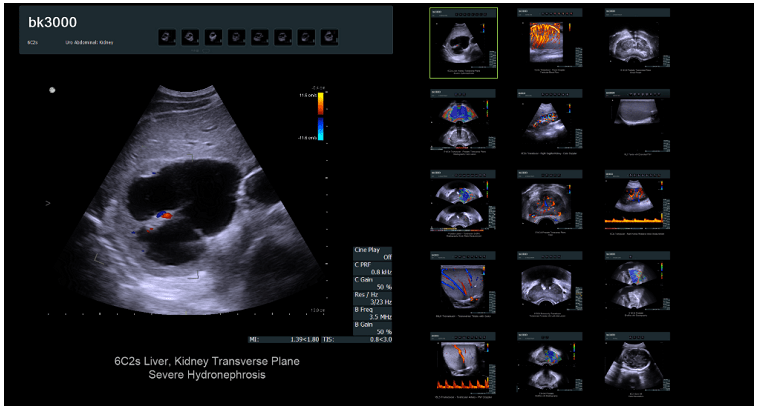

這種資源與類似資源之間的主要區別可以是產品卡。如果產品足夠簡單,例如出售藥品,消耗品,則卡的要求是標準的。但是,如果出售復雜的設備或昂貴的產品,則該卡的外觀和功能可能會完全不同。這是一個醫療網站例子。

該在線商店出售現代且昂貴的設備(超聲波機器)。目標受眾不需要號召性用語,不需要標準的潛在客戶生成按鈕或評論形式的信任塊。產品的詳細和專業描述在這里起著關鍵作用,它將表明其功能,功能和優勢。

同意,此產品卡與我們以前所見的產品根本不同。但同時,它完全可以滿足目標受眾的需求。用于聯系賣家的潛在客戶生成按鈕促成銷售,并允許您增加網站的轉化率。